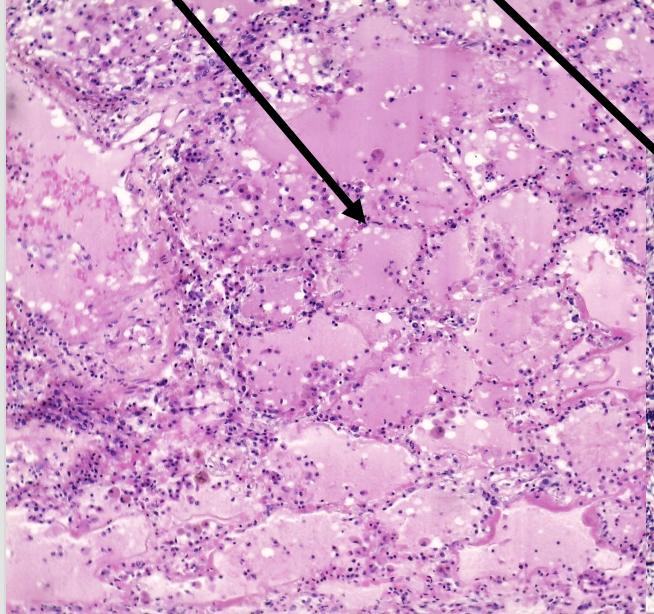

pathologische verschillen bij tuberculose van de long

alveoli:

oedeemvocht

inflammatoir infiltraat, vnl. macrofagen

luchtvacuolen

benoem de pijlen van links naar rechts+ waarover het gaat

macrofagen

—> alveoli; tuberculose van de long

welke kleuring is niet genoeg om de diagnose tuberculose van de long te stellen+ wat moet je doen voor diagnose

H&E kleuring

aanwezigheid van Koch-bacil kunnen aantonen adhv Ziehlsen kleuring of Auraminekleuring

effect Ziehlsen kleuring

de zuurvaste Koch-bacillen kleuren rood

effect Auramine

de bacillen kleuren fluorescent

basisletsel tuberculose long

granulomateuze ontsteking waarbij centrum necrotiseerd en er caseëuze necrose w gevormd